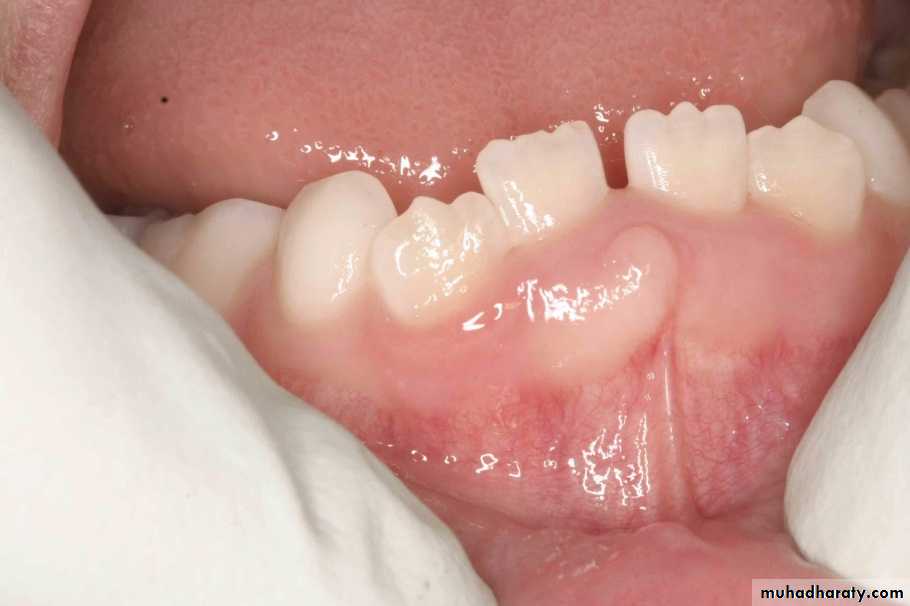

pyogenic granuloma

• Is a benign, elevated, and capillary-rich lesionIs, soft, red or purple mass on the lips, interdental papilla, or buccal mucosa .• It may occur in the skin.

• The cause is thought to be local irritation, hormonal factor or trauma.

• When located at the gingiva of pregnant women, the term pregnancy tumor may be used.

• Histologic evaluation shows granulation tissue with numerous

endothelium-lined vascular spaces and fibroblasts.

pyogenic granuloma• An oral pyogenic granuloma most frequently involves the gingiva.

• The lower lip and the dorsal surface of the tongue are rather common sites as well.• The lesion is usually pedunculated or sessile, and the surface is often ulcerated.

• The size of the lesion's diameter may vary from 0.5 to 2 cm or more.

• Sometimes rising the question of whether one is dealing primarily with a vascular lesion with secondary signs of inflammation or with an inflammatory condition.

• Mitotic activity may be abundant and should not be mistaken as a sign of malignancy.

• Surgery is the management of choice. Recurrence rare.